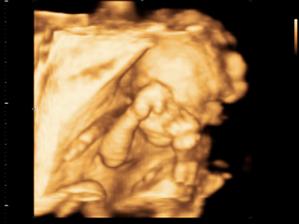

Naše druhé Slniečko